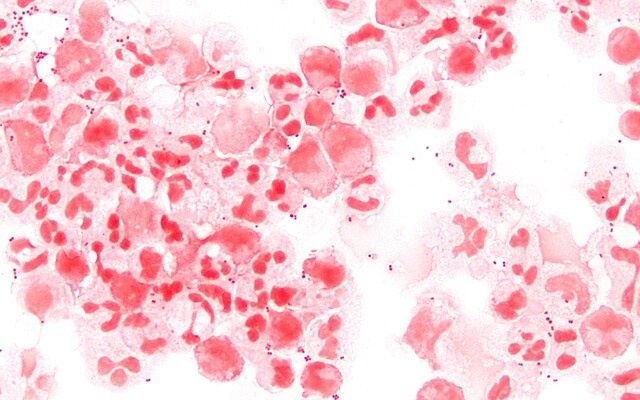

В РФ наблюдается рост случаев менингококковой инфекции, сопровождающийся увеличением вероятности смертельных исходов. По информации "Коммерсанта", ссылающегося на комитет Госдумы по охране здоровья, ключевым фактором является трудовая миграция населения.

Ранее менингококк представлял собой проблему преимущественно детского возраста. В настоящее время болезнь всё чаще диагностируется у взрослого населения. За первые пять месяцев 2025 года было зафиксировано 1266 случаев инфицирования (из которых 948 – у взрослых). Это демонстрирует увеличение на 260% по сравнению с тем же периодом предыдущего года.